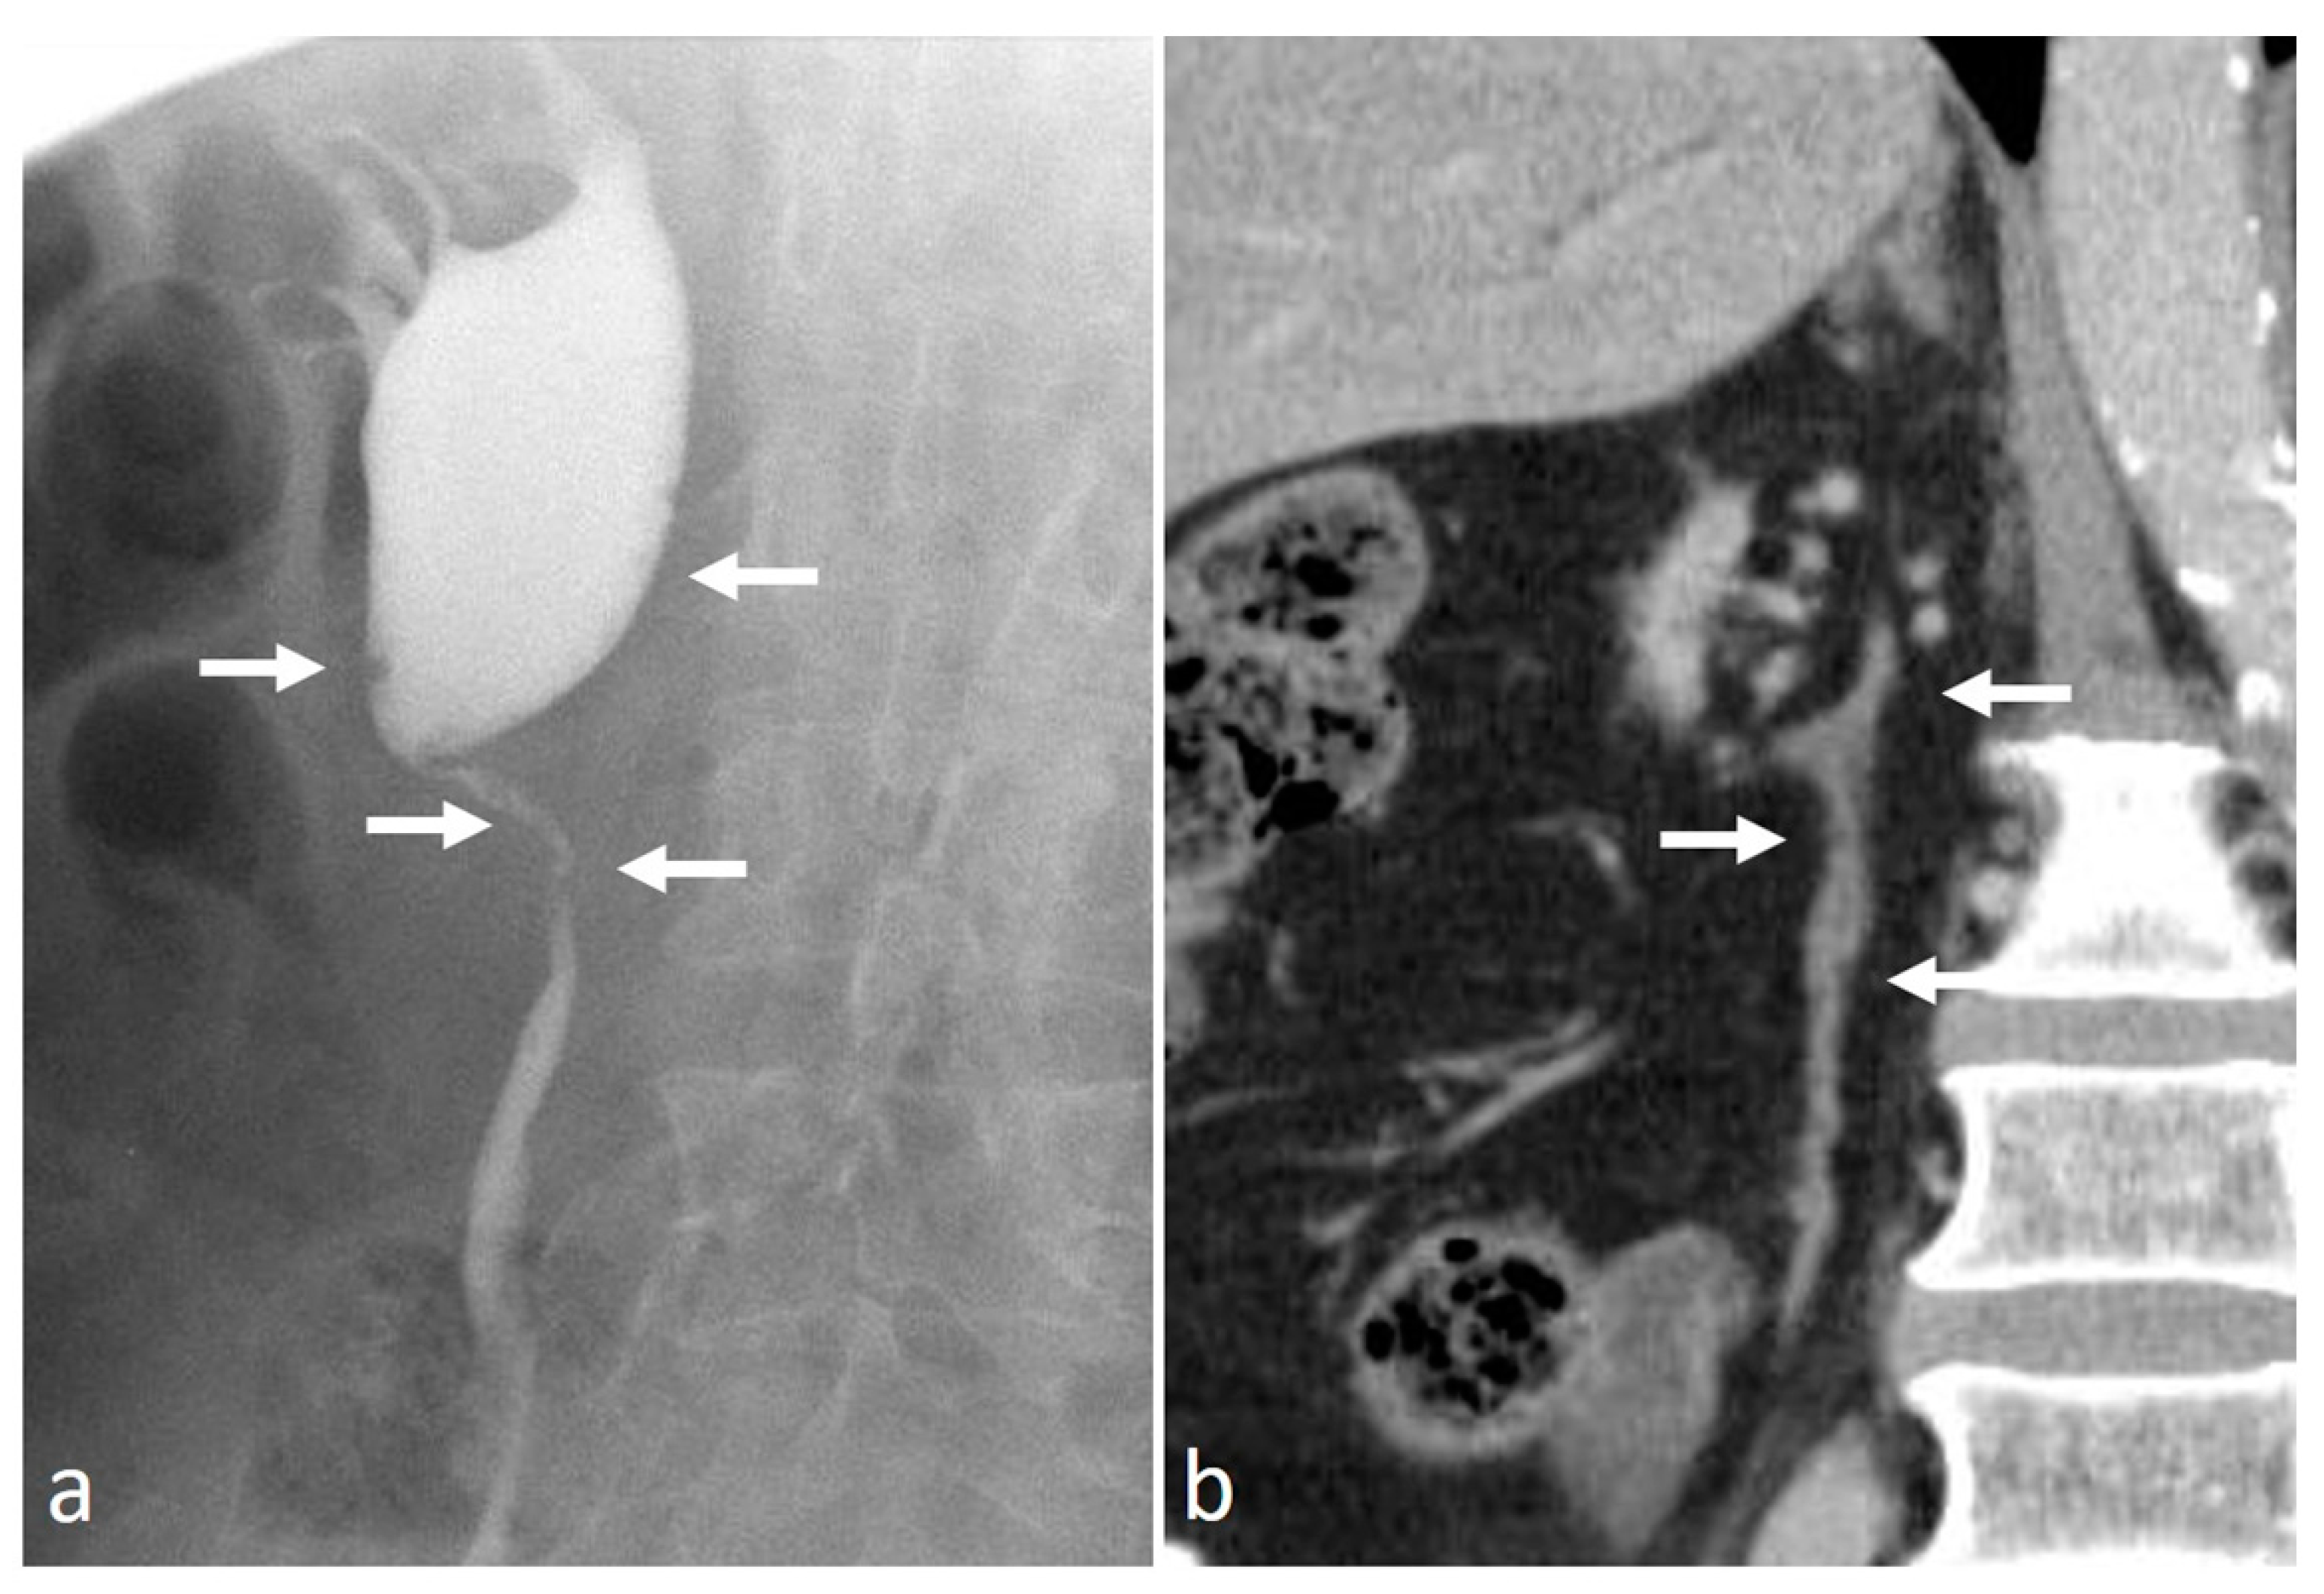

4.6. Retroperitoneal Fibrosis

4.7. Pyeloureteritis Cystica